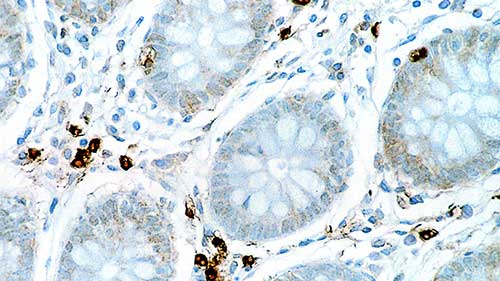

Human placenta: immunohistochemical staining for CD163. Note cytoplasmic staining of Hofbauer cells. CD163: clone 10D6

The CD163 molecule is a type I membrane protein also known as M130 antigen, Ber-Mac3, Ki-M8 or SM4. CD163 protein is restricted in its expression to the monocytic/macrophage lineage. It is reported to be present on all circulating monocytes and most tissue macrophages except those found in the mantle zone and germinal centers of lymphoid follicles, interdigitating reticulum cells and Langerhans cells. In addition, multi-nucleated cells within inflammatory lesions are reported not to express CD163 protein. The protein is upregulated by glucocorticoids and downregulated by the immunosuppressant cyclosporin A and by phorbol esters, while lipopolysaccharide, an inflammatory mediator, has no influence on expression. It has been proposed that a specific release mechanism of soluble CD163 antigen by human monocytes may play an important role in modulating inflammatory processes.